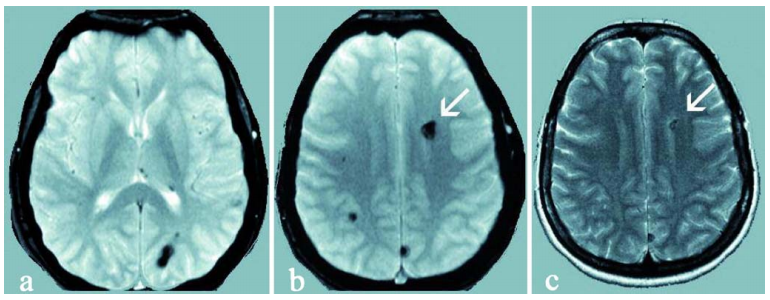

经抗水肿治疗后,患儿临床状况趋于稳定,神经症状短期内有所改善。但后续MRI检查显示原发病灶已增长至4×3.5×3cm,同时在左额叶及顶叶发现继发性致痫灶,病理类型同为海绵状血管瘤。

多发病灶提示存在家族遗传可能。基因检测证实患儿及其母亲均携带CCM1基因新发突变。母亲MRI虽显示多发性海绵状血管畸形病灶,但未见临床症状表现。

由巴教授主刀完成病灶全切手术,术中应用体感诱发电位及脑干听觉诱发电位监测,结合神经导航技术实现精准切除。术后十日MRI证实病灶完全切除,脑干受压解除,第四脑室形态恢复正常。患儿神经功能持续改善,后续接受系统化神经康复治疗。